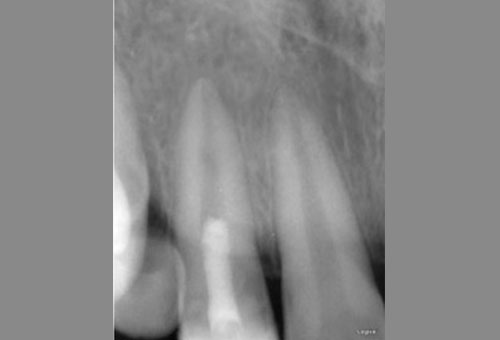

Long cone periapical radiograph of tooth 12 one month after injury